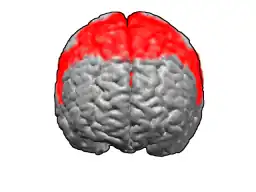

Brodmann area 6 (BA6) is part of the frontal cortex in the human brain. Situated just anterior to the primary motor cortex (BA4), it is composed of the premotor cortex and, medially, the supplementary motor area (SMA). This large area of the frontal cortex is believed to play a role in planning complex, coordinated movements.

Brodmann area 6 is also called agranular frontal area 6 in humans because it lacks an internal granular cortical layer (layer IV). It is a subdivision of the cytoarchitecturally defined precentral region of cerebral cortex. In the human brain, it is located on the portions of the precentral gyrus that are not occupied by Brodmann area 4; furthermore, BA6 extends onto the caudal portions of the superior frontal and middle frontal gyri. It extends from the cingulate sulcus on the medial aspect of the hemisphere to the lateral sulcus on the lateral aspect. It is bounded rostrally by the granular frontal region and caudally by the gigantopyramidal area 4 (Brodmann, 1909).[1]

Image

-

Animation.

Animation. -

front view.

front view. -